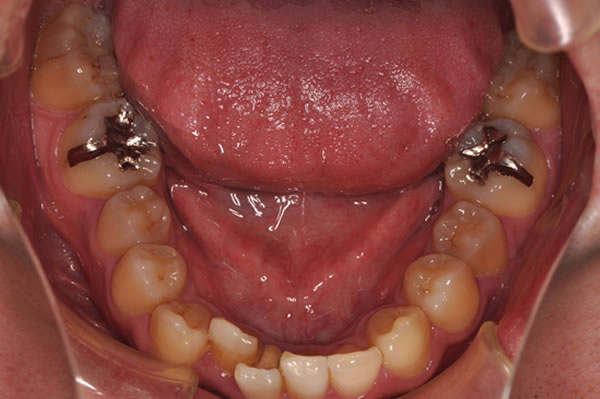

唇側矯正の治療例

反対咬合症例

治療前(初診)

治療後